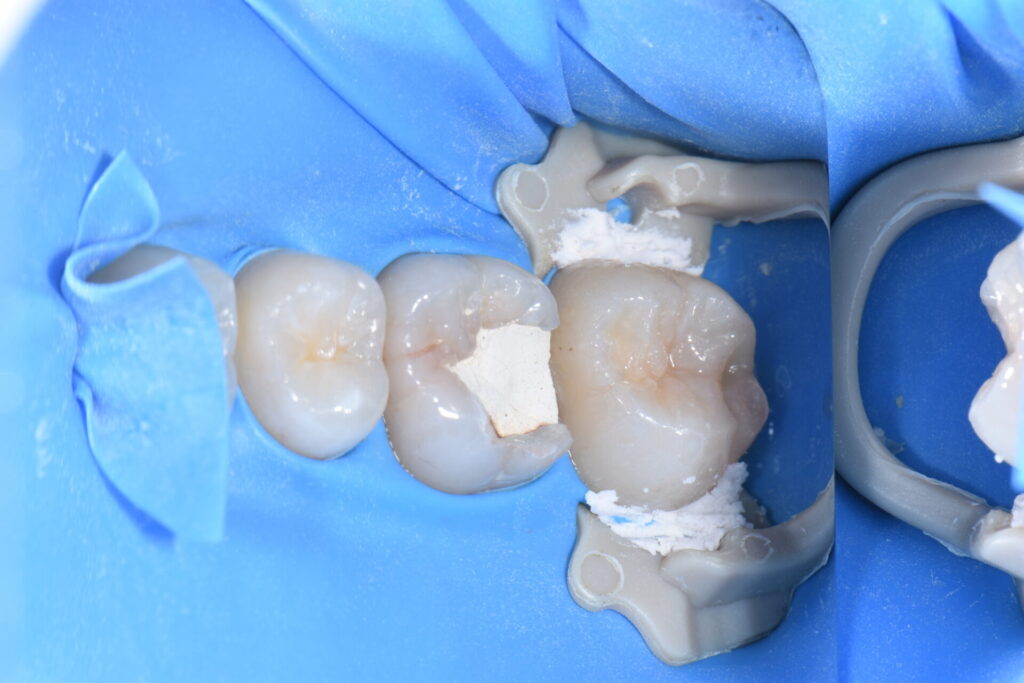

術前 歯科健診と歯のクリーニングで来院。第二大臼歯に虫歯が見つかりました。

無自覚無症状で大変小さな虫歯に見えますが実は大きな虫歯です。

術中 虫歯を除去していくと

術中 神経にまでおよぶ深い虫歯でした。赤く出血しているところが神経です。

当院では虫歯は細菌感染であり綺麗に除去しなけらばならないと考えています。

ラバーダム防湿下で呼気や唾液、口腔内細菌にさらされることなく処置すれば高確率で

神経を温存できます。

神経を取らずにMTAで歯髄を保護しダイレクトボンディング修復していきます。

術後 何日間か冷水痛・咬合痛を出ましたが経過は良好です。

最小限の治療介入で処置を終えることが出来ました。無自覚無症状で虫歯や歯周病は進行していきます。定期的な歯科健診と歯のクリーニングで口腔内を健康な状態に保つことは全身の健康のためにも重要です。

費用は神経を守る処置 MTA ¥10.000 ダイレクトボンディング¥30.000(税別)